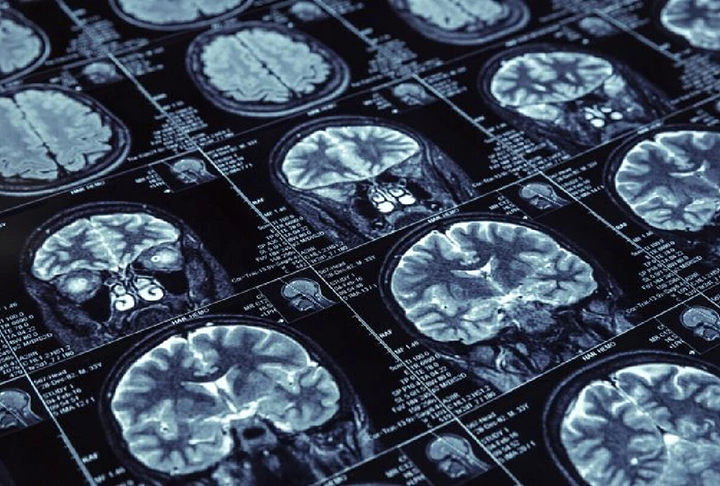

Mundo em alerta sobre Alzheimer: em 2050, doença deve afetar 139 milhões de pessoas